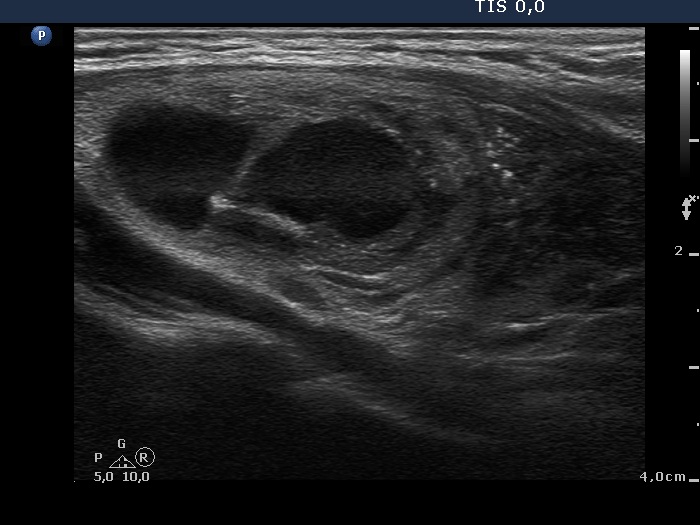

Papillary carcinoma (histological diagnosis) |

This case is less edifying or may be more edifying. Compared with the previous case, the granules here are less bright. Nevertheless, great proportion of them belong to punctate echogenic foci (arrows). It is worth to compare these with non-specific granules (arrowheads). |